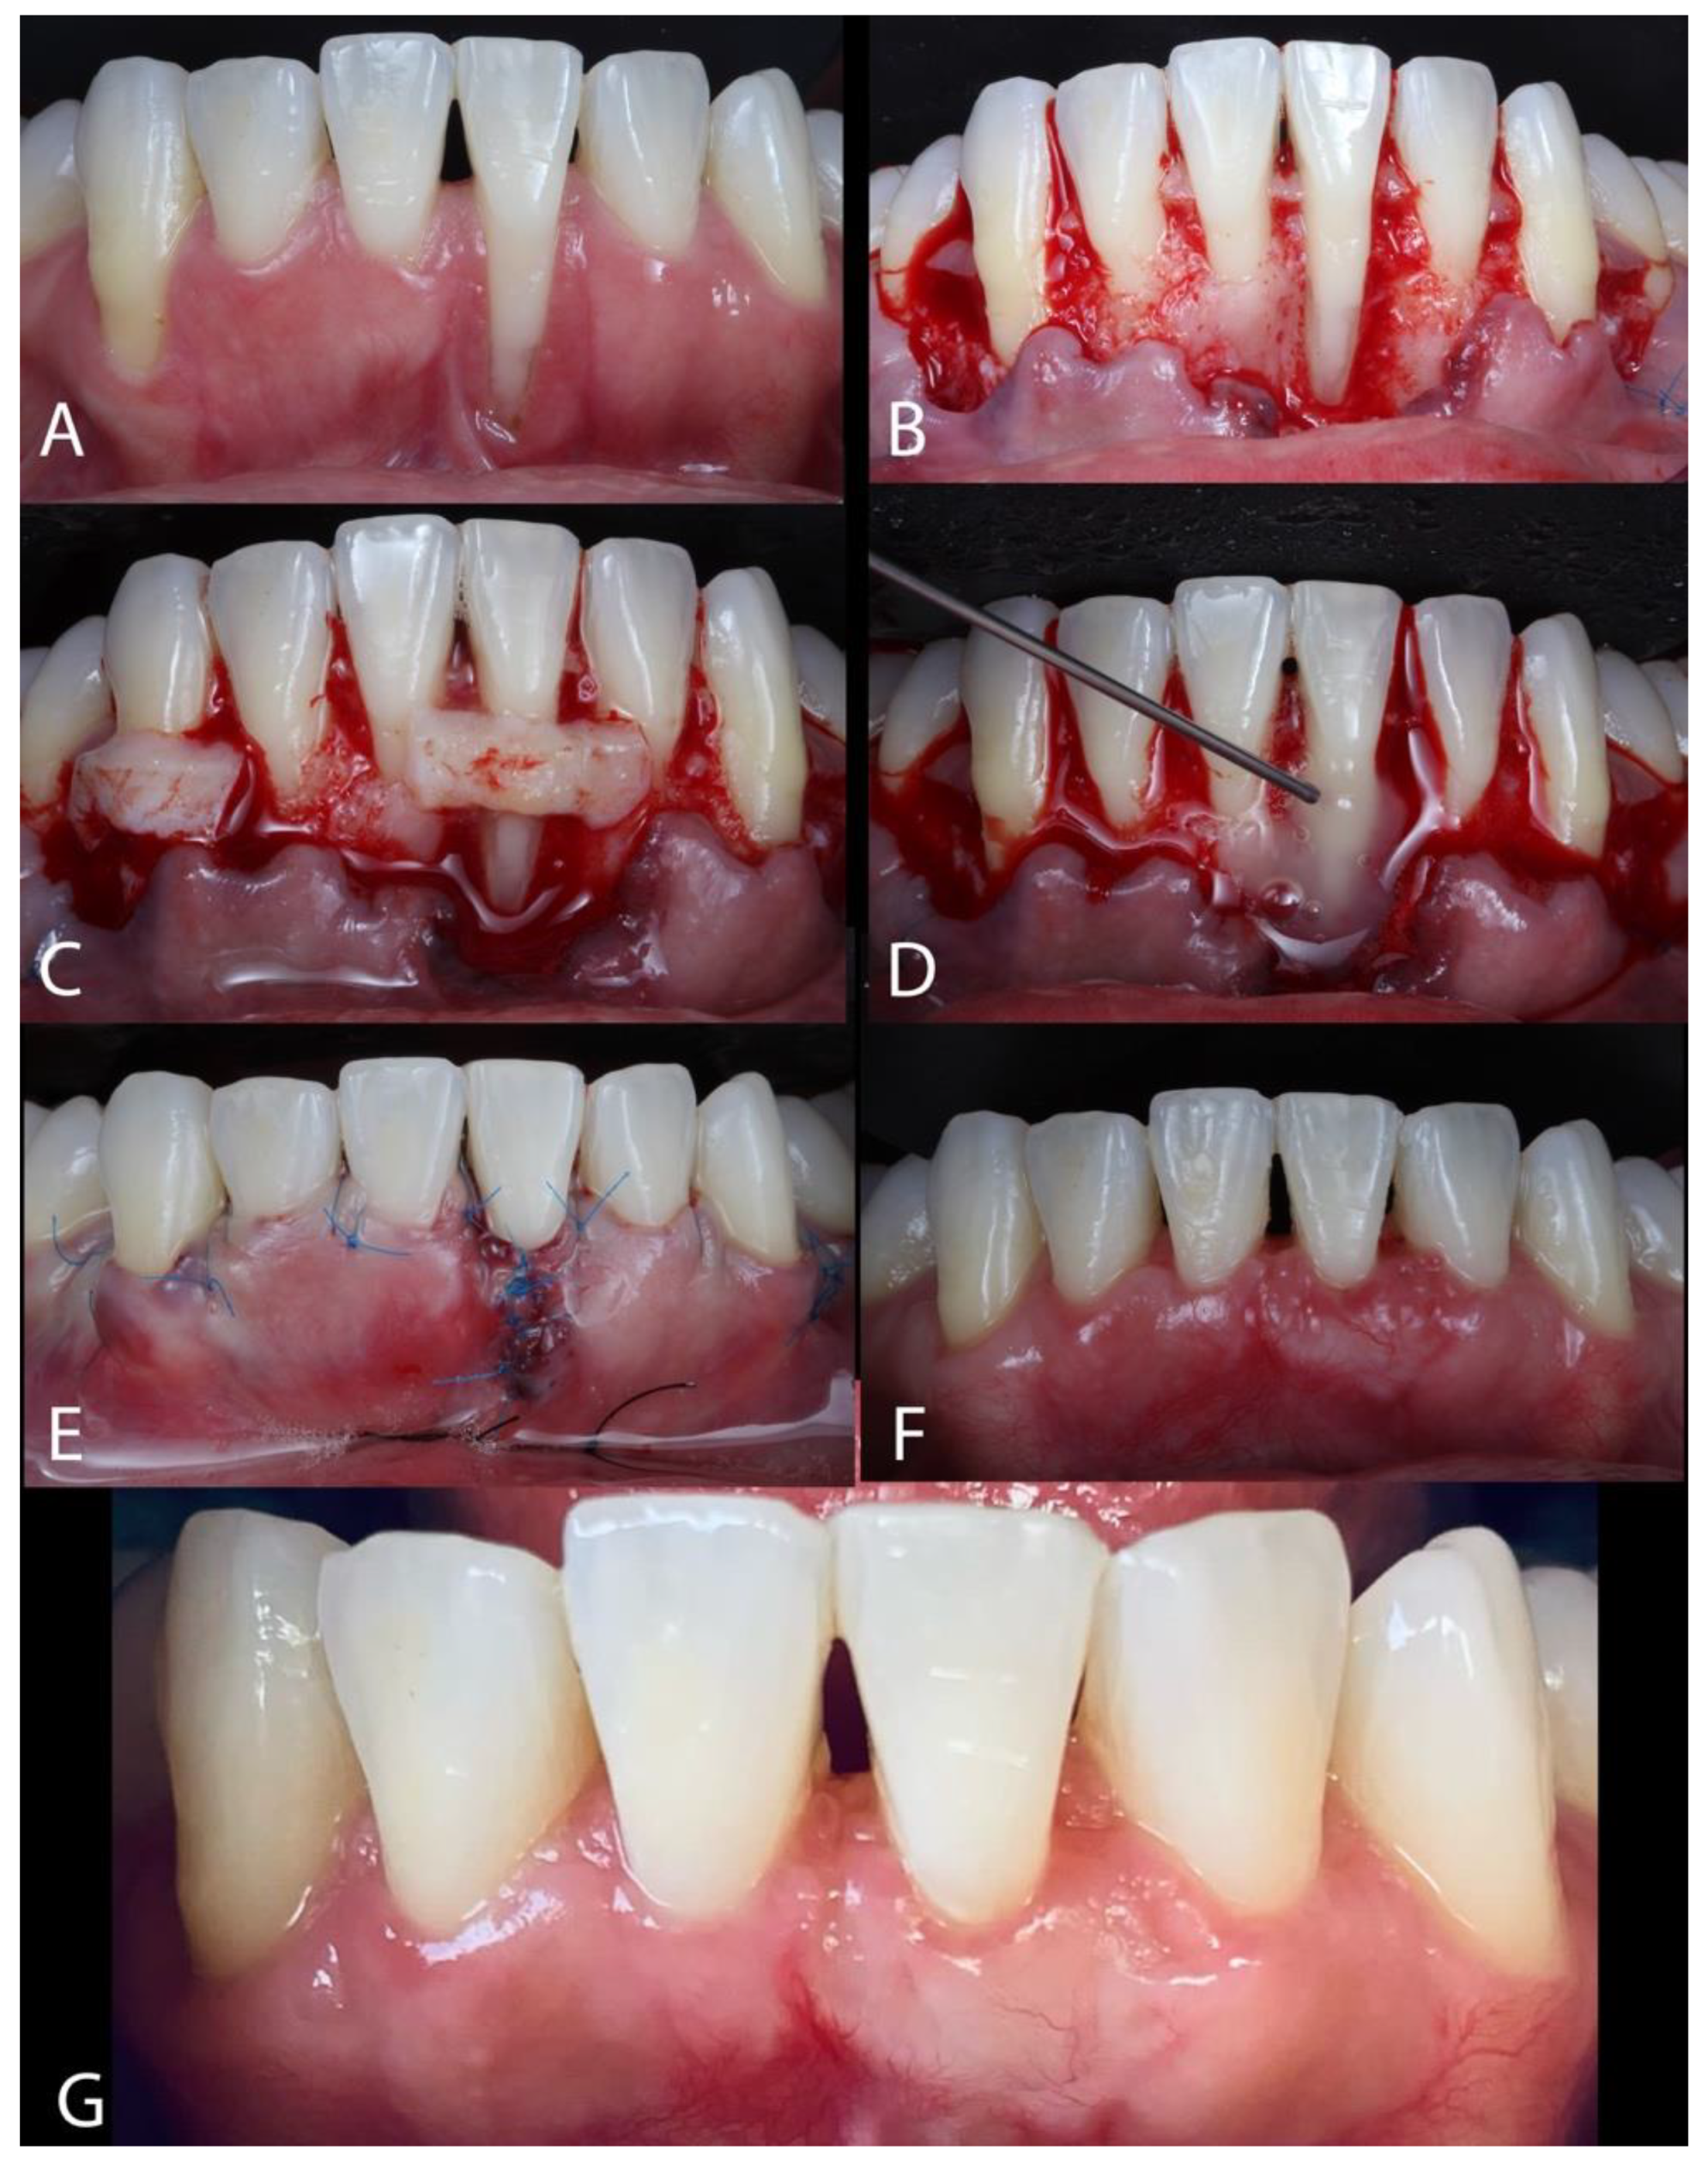

The Treatment of Gingival Recessions in the Lower Anterior Region Associated with the Use/Absence of Lingual-Fixed Orthodontics Retainers: Three Case Reports Using the Laterally Closed Tunnel Technique and Parallel Incision Methods

- Sculean, A.; Allen, E.P. The Laterally Closed Tunnel for the Treatment of Deep Isolated Mandibular Recessions: Surgical Technique and a Report of 24 Cases. Int. J. Periodontics Restor. Dent. 2018, 38, 479–487. [Google Scholar] [CrossRef] [PubMed]

- Kahn, S.; Araujo, I.T.E.; Dias, A.T.; Souza, A.B.; Chambrone, L.; Fernandes, G.V.O. Histologic and histomorphometric analysis of connective tissue grafts harvested by the parallel incision method: A pilot randomized controlled trial comparing macro- and microsurgical approaches. Quint. Int. 2021, 52, 2021. [Google Scholar]

2. Materials and Methods

3. Results